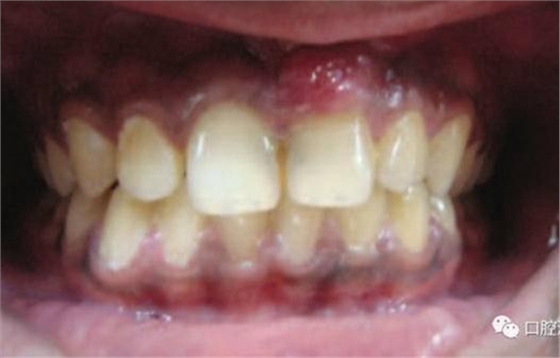

11、21 治療前